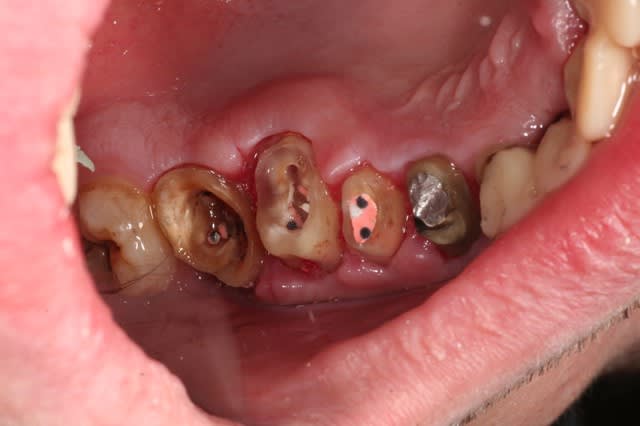

un cas comme je les aime......

le traitement poursuit son bonhomme de chemin..

une vue du côté droit après élongation coronaire à une semaine...

à suivre..